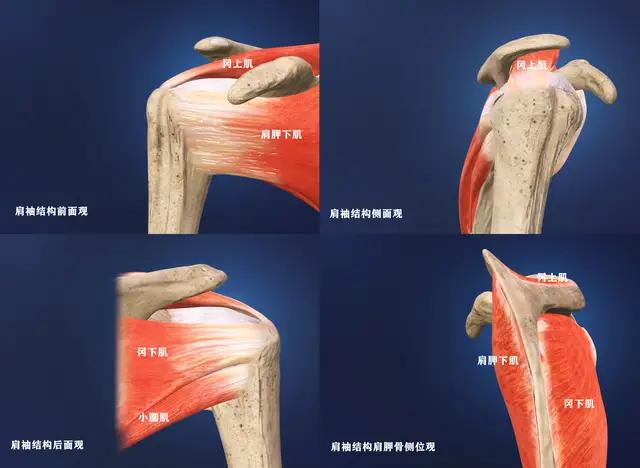

●肩袖损伤:肩袖是一个非常复杂的结构,我们通常也称之为旋转袖,分别由冈上肌,冈下肌,肩胛下肌以及小圆肌的肌腱构成。肩袖对于肩关节的整个活动起到了非常重要的作用,同时还有稳定肩关节的作用。

导致肩袖损伤的原因有很多,比如外伤、比如退化、比如肩关节撞击。

肩袖出现损伤的患者,疼痛比较明显,在夜间的时候可能会出现明显的加重,而且患者有可能出现典型的“疼痛弧”,也就是活动到一定角度的时候疼痛开始出现,但随着角度的加大,疼痛慢慢的减轻了,有一些患者随着病情时间的延长,会出现肩关节的肿胀,出现肩关节的粘连!

诊断:对于肩袖损伤的诊断,首先患者要有相应的症状,要去医院寻求医生的帮助,医生要进行相应的查体之后,根据患者的症状结合自己的查体进行核磁检查,来明确是否存在肩袖损伤的症状、查体以及核磁互相印证的时候就可以做出确定诊断。

治疗:如果疼痛不是特别严重,肩关节粘连不是特别的明显,肩袖不是全层撕裂的话,可以采取保守治疗。可以通过口服或者是外用非甾体抗炎镇痛药帮助患者控制疼痛,可以通过专业医生的手法治疗,放松紧张的肩关节周边的肌肉,对于有粘连的患者可以通过手法治疗进行松解,帮助患者恢复更好的肩关节活动角度。可以采取局部封闭注射的办法,帮助患者控制疼痛和关节内的炎症反应。

但如果是肩袖全层撕裂,患者疼痛比较明显,肩关节的功能严重受限,而且患者有主观意愿,想要解决问题的时候,需要进行肩关节镜手术治疗,对肩袖进行缝合或者是止点重建。